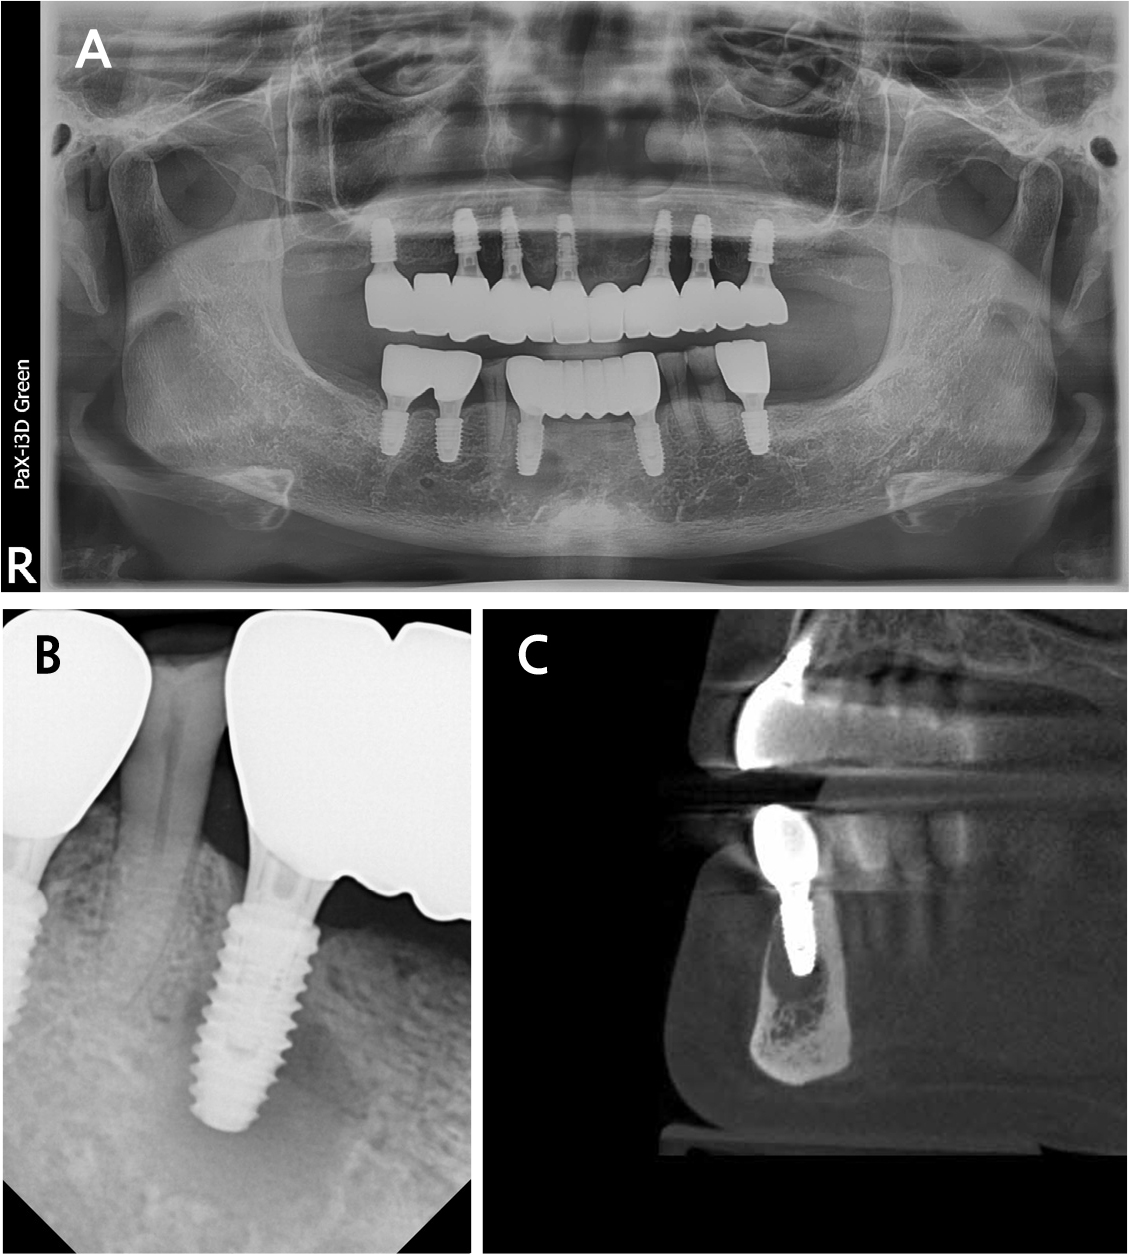

A 62-year-old female presented to the Department of Periodontology in Dankook University Dental Hospital with complaints of tenderness and a fever-like sensation around implant #43. A sinus tract was noted at the mesial aspect of the buccal peri-implant mucosa. Pocket probing depth ranged from 1–3 mm without bleeding. Panoramic and intraoral radiographs, along with cone-beam computed tomography (CBCT), showed intact crestal bone, a periapical radiolucency mainly involving the buccal aspect and extending lingually, and a thinned buccal bone with a 2 mm fenestration (Fig. 1). Adjacent tooth #44 responded normally to cold and electric pulp tests. The patient had a history of rheumatoid arthritis and allergies to sulfonamides and Penicillin. Her dental history included root canal treatment on #43, extractions owing to advanced bone loss (#15–13, 24, 33, 36, 37, 43, 45, 46), and implant treatment performed 1.3 years earlier using static computer-assisted surgery (Neo NaviGuide; Neobiotech, Wonju, Korea) (Fig. 2). A provisional diagnosis of RPI was made. A reconstructive surgical approach via the buccal aspect was planned.